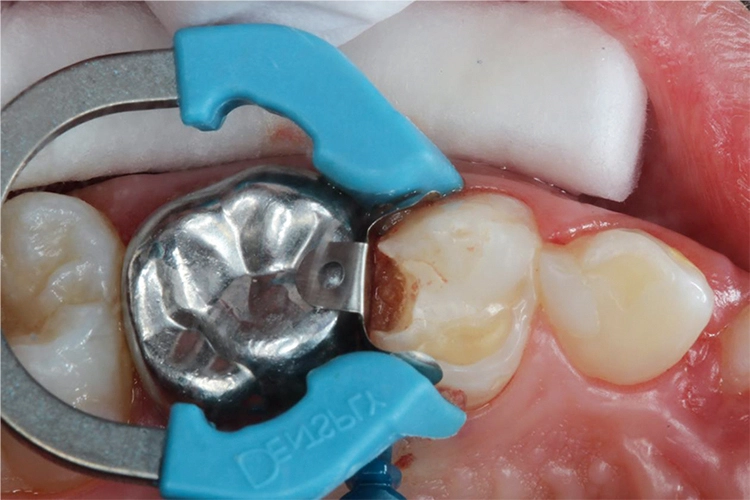

Möhn, KrämerHierfür wurde die Kavität zunächst mit einem birnenförmigen Diamanten aufgezogen und das kariöse Dentin mit einem Polymerbohrer schonend exkaviert (Abb. 3). Für die Formgebung und den Schutz des Nachbarzahnes wurde das Teilmatrizensystem Palodent® V3 verwendet (Abb. 4). Im Anschluss folgte die Füllungstherapie mittels Surefil one™ in Farbe A2.

Möhn, KrämerHierzu wurde das Kapselpräparat per Hand auf einer stabilen Unterlage aktiviert und für 10 Sek. in einem Kapselmischer vermischt. Die Applikation des selbstadhäsiven Materials in die Kavität erfolgte in einem Schritt (Abb. 5).

Möhn, KrämerDank der modifizierten Polysäuren des verwendeten Komposithybrids konnte auf eine adhäsive Vorbehandlung des Zahnes verzichtet werden. Anschließend wurden die Überschüsse mittels Kugelstopfer entfernt (Abb. 6) und jede Fläche für 20 Sek. polymerisiert (SmartLite® Pro).

Möhn, KrämerDie Oberfläche kann dadurch direkt nach der Lichthärtung ausgearbeitet werden, während das Material noch in der Tiefe chemisch vollständig aushärtet. Das Abschlussbild zeigt die fertige Restauration nach Ausarbeitung und Politur (Abb. 7).